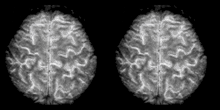

Cognitive neuroscience aims to reduce cognition to its neural basis using new technologies such as fMRI, repetitive transcranial magnetic stimulation (rTMS) and Magnetoencephalography (MEG) as well as older methods such as Positron emission tomography (PET) and Electroencephalography (EEG) studies. Due to the correlational designs used in fMRI, many scientists have coined this up and coming field as the new phrenology in the sense that techniques such as fMRI rely heavily on complex statistics.[17] Type 1 errors can lead scientists to draw premature and incorrect causal relationships if improper designs are used.[18]

Functional magnetic resonance imaging (fMRI) has intriguing implications for the study of memory in humans, however it can also be used in animal models. fMRI can be used to assess brain functionality in monkeys in the context of a variety of behavioral tasks.[26] Structural MRI can be used to examine the extent and location of brain lesions, so that behavioral abnormalities observed can be directly linked to specific brain structures.[27] High-resolution fMRI can help locate and assess the functionality of large neural networks so that these regions can be further studied using more traditional electrophysiological recording devices.[26]